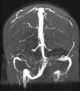

Congenital sinus hypoplasia